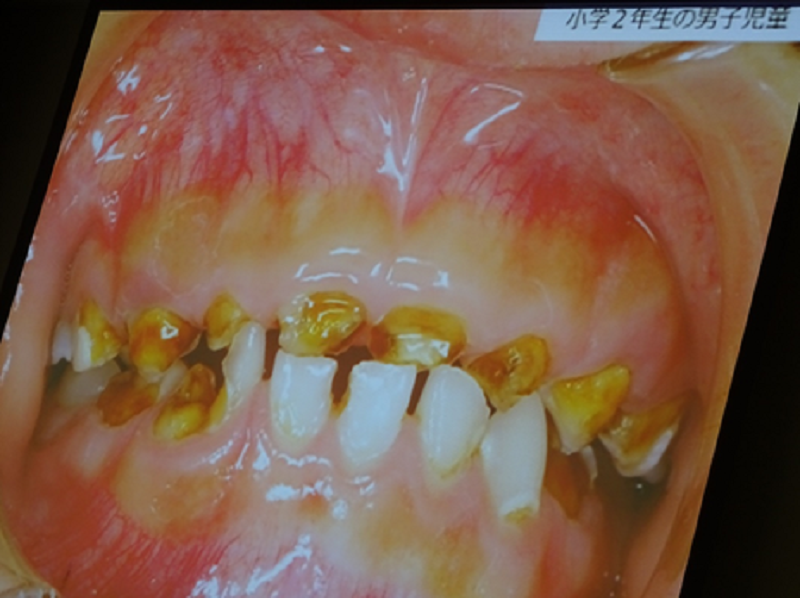

歯科医師 戸井逸美氏講演。(以下)

小学2年生、虫歯ばかり0126_07